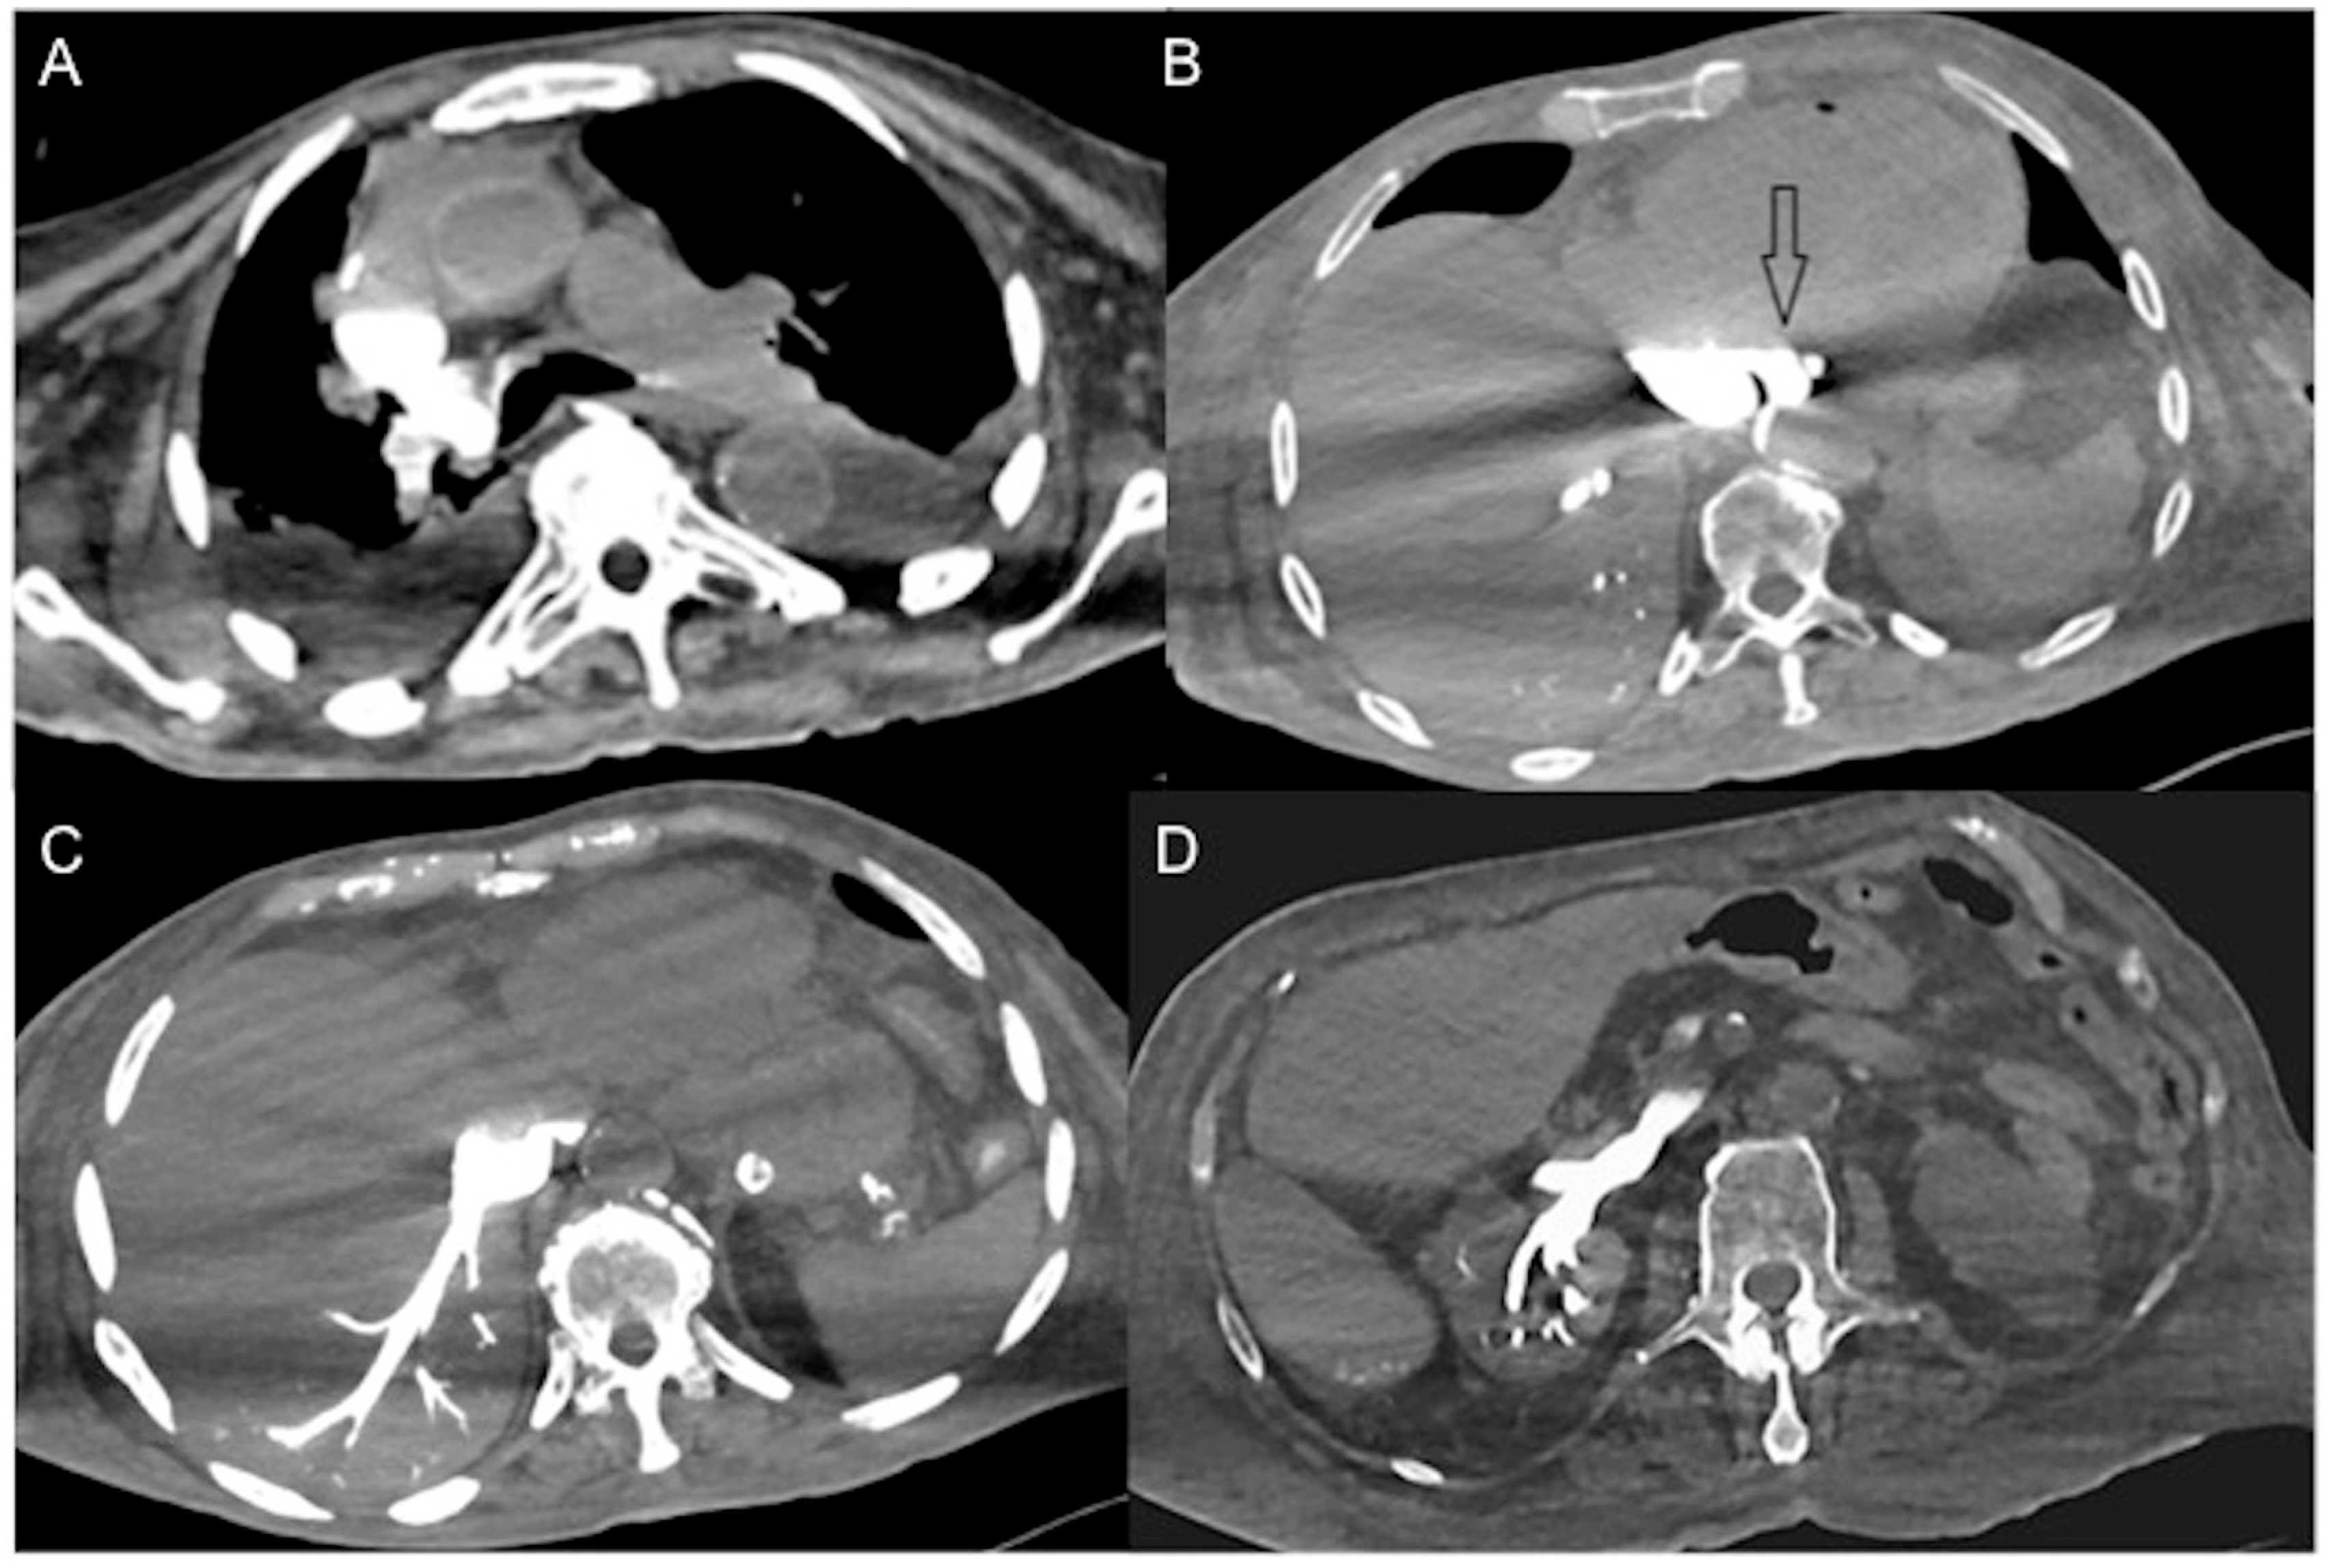

- In irreversible end-organ dysfunction, injected IV CM circulation is supported only by the pressure applied by the automated power injector and the density of contrast material. Circulatory arrest leads to dense contrast pooling and layering in the SVC, IVC (inferior vena cava), and right heart chambers with non-opacified left heart chambers or arterial vessels (Figure 1) [43,45,49,50,51,52]. This may be called the “non-beating heart” pattern. Cardio-pulmonary aggressive resuscitation must immediately be initiated within the framework of a predetermined emergency plan.

- There is the presence of a slit-like or flat inferior vena cava (FIVC) (Figure 2A). This is characterized by an anterior-posterior diameter of less than 9 mm in three consecutive segments, 20 mm above and below the renal veins, and at the level of the perihepatic region. Additionally, a transverse-to-anteroposterior ratio of ≥2.5 at the level of the suprarenal IVC can indicate flattening. The flatness index or IVC diameter ratio is calculated by dividing the maximal transverse and anteroposterior diameters of the IVC [15,16,17,18,19,20,21,22,23,24,25,26,27,28,29,30,31,32,57,58,59,60,61].

- The IVC halo sign is characterized by a low attenuation band (<20 HU) encircling the collapsed intra- and retrohepatic inferior vena cava. This band is caused by a ring or rim of edema [65,66,67]. In cases of severe hypovolemia, approximately 80% of patients may exhibit this sign, resulting from the loss of precapillary arteriolar sphincter tone and the accumulation of fluid surrounding the IVC (Figure 2B–D) [18,25,30,31,65,66,67]. However, it is important to note that this sign is not specific to non-traumatic patients and can also be observed in conditions such as liver congestion, biliary cirrhosis, hepatitis, or other diseases that obstruct lymphatic drainage at the porta hepatis [25].